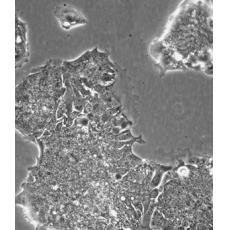

中文名稱 人結(jié)腸腺癌肺轉(zhuǎn)移細(xì)胞

組織來源 結(jié)腸腺癌;肺轉(zhuǎn)移;男性

細(xì)胞種屬 Homo sapiens, human

生長特性 adherent

形態(tài)特征 epithelial

細(xì)胞描述 T84細(xì)胞株是從一位72歲男性結(jié)腸癌患者的肺轉(zhuǎn)移灶建立的可移植人類癌細(xì)胞株。 腫瘤組織皮下接種于BALB/c裸鼠,并連續(xù)進(jìn)行移植。 [26072] 在裸鼠身上的移植過程中,細(xì)胞株始終保持結(jié)腸癌的原始組織性狀。 [26072] 在無胸腺小鼠中傳代23代后建立了T84細(xì)胞株。 這些細(xì)胞單層生長到飽和并在接觸細(xì)胞間展現(xiàn)出緊密連接和橋粒。 [1155] 有很多關(guān)于多肽類激素和神經(jīng)遞質(zhì)并維持定向電解質(zhì)傳輸?shù)氖荏w。 [1155] 這株細(xì)胞展現(xiàn)了接觸細(xì)胞中的緊密連接和橋粒。 [1155] 角蛋白免疫過氧化物酶染色陽性。